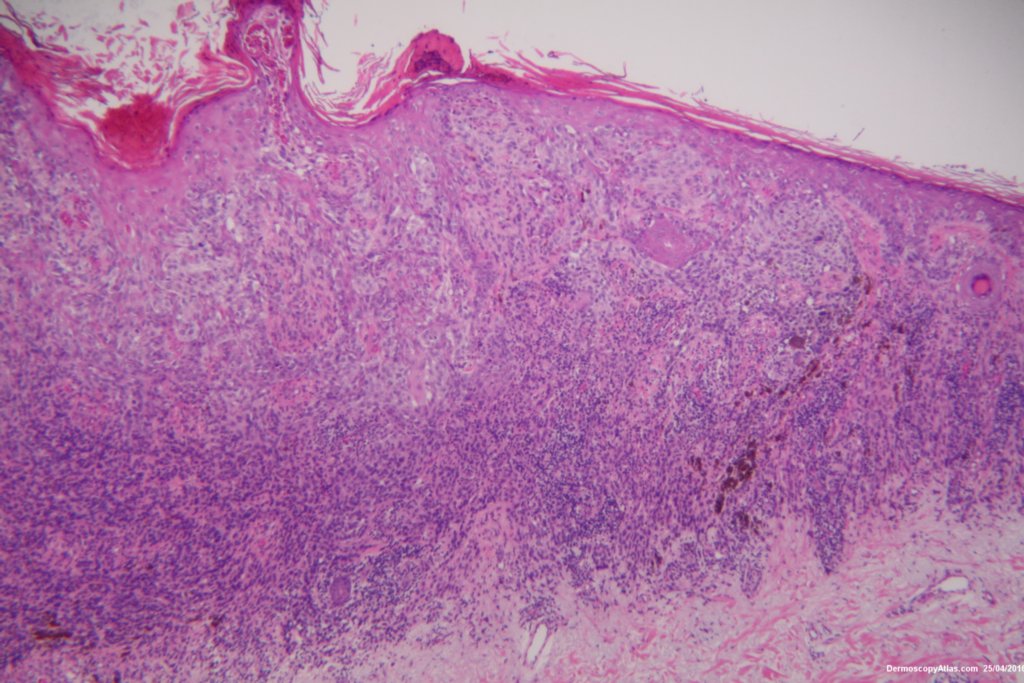

The shave biopsy was reported as a level 4 Invasive melanoma 1.7 mm thick with 3 mitoses per high powered field. There were no groin glands enlarged clinically.